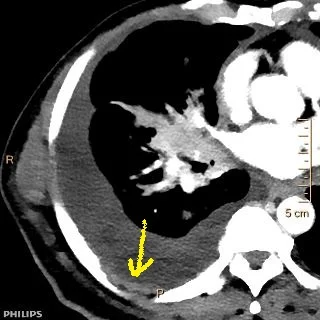

67 yo M presented with cough and shortness of breath. Conventioanl CT shows large right pleural effusion. On 40 keV image, large pleural nodule becomes obvious. Note the central mass.

Conventioanl CT shows large pleural effusion on the right. Note the central mass.

40 keV image clearly depicts the pleural tumor deposit.